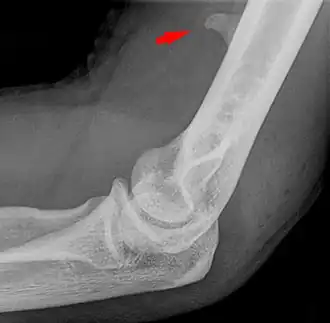

Larger supracondylar process seen on a lateral radiograph of the elbow

The supracondylar process of the humerus (also known as an avian spur) is a variant bony projection on the anteromedial aspect of the upper arm bone (humerus), about 5–6 cm above the medial epicondyle.[1] It is directed downward, forward and medially pointing to the medial epicondyle. A fibrous band, Struthers ligament, may connect this process to the medial epicondyle.[2] This variation has a prevalence of 0.68% and is significantly more common in women than in men.[3]